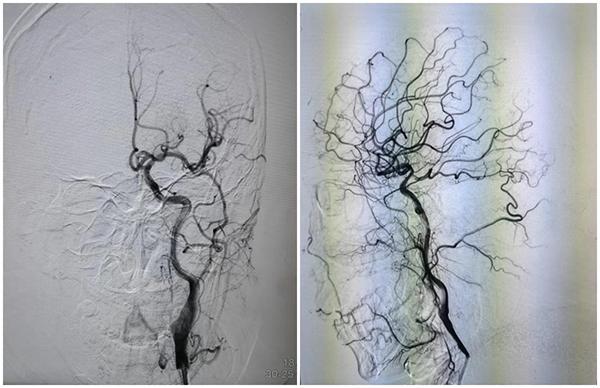

“時(shí)間就是大腦”,腦梗死救治分秒必爭(zhēng)。按照防疫要求,徐醫(yī)附院緊急啟動(dòng)“綠色通道”,為其進(jìn)行核酸采樣,經(jīng)卒中救治團(tuán)隊(duì)李海亮主治醫(yī)師對(duì)患者進(jìn)行檢查評(píng)估:患者意識(shí)喪失,右側(cè)偏癱,雙眼向左側(cè)凝視,既往有心臟瓣膜病換瓣手術(shù)史,長(zhǎng)期口服華法林治療,考慮心源性栓塞可能。于是緊急啟動(dòng)腦血管病介入應(yīng)急小組,卒中病區(qū)程言博主任醫(yī)師、杜波副主任醫(yī)師火速趕到,急診上臺(tái)動(dòng)脈取栓,手術(shù)過(guò)程復(fù)雜艱辛,但是憑借豐富的經(jīng)驗(yàn)和嫻熟的技藝,一把取通,及時(shí)恢復(fù)前向血流。病人術(shù)后意識(shí)立即恢復(fù)至清醒,癱瘓側(cè)肢體能自主活動(dòng)。

術(shù)前血管

術(shù)后血管